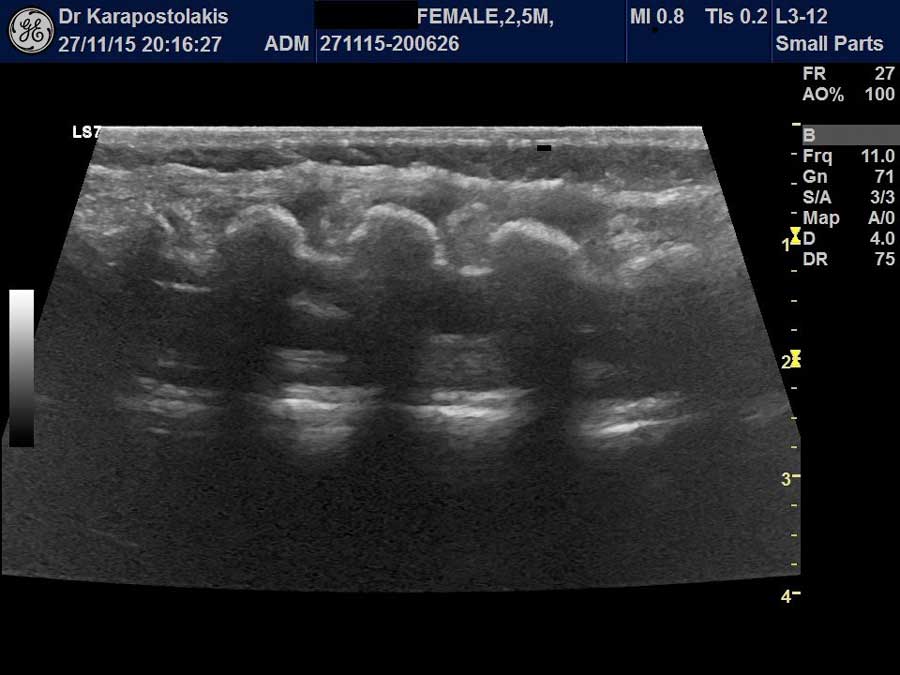

- Υπερηχογράφημα οισοφάγου-στομάχου (ΓΟΠ,υπερτροφική πυλωρική στένωση)

- Υπερηχογράφημα δεξιού λαγονίου βόθρου (σκωληκοειδής απόφυση, τελική ειλεϊτιδα, μεκέλειος απόφυση), εντέρου (για εγκολεασμό, ΙΦΝΕ)

- Υπερηχογράφημα άνω μεσεντερίων αγγείων (malrotation)